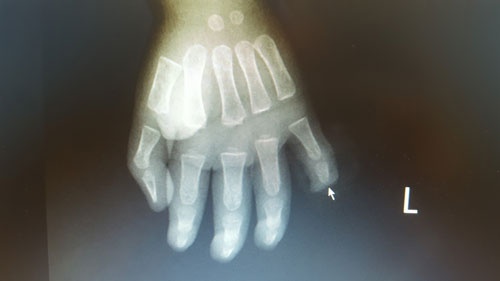

Phim chụp X-quang bàn tay trái của bệnh nhi. Ảnh: BVCC.

Trẻ nhập viện với vết thương đứt rời đốt số 3 ngón 5 bàn tay trái, chảy nhiều máu. Các bác sĩ khoa Chấn thương - Chỉnh hình và Bỏng đã tiến hành phẫu thuật tạo mỏm cụt ngón tay số 5 cho trẻ. Hiện, bé Q. sức khỏe đã ổn định.